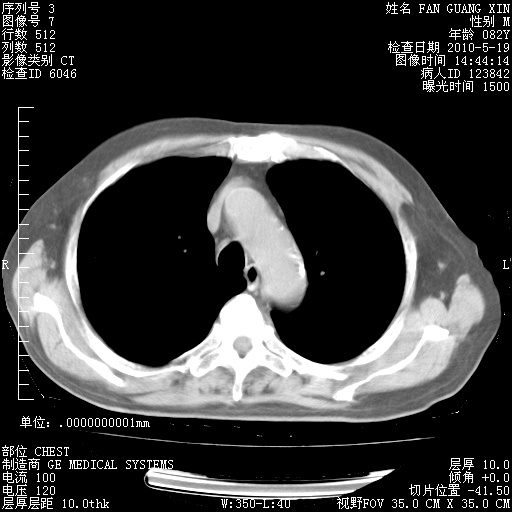

复查肺部CT,明显好转。为什么发热呢?

治疗3周后的肺部CT

治疗3周后的肺部CT纵隔窗